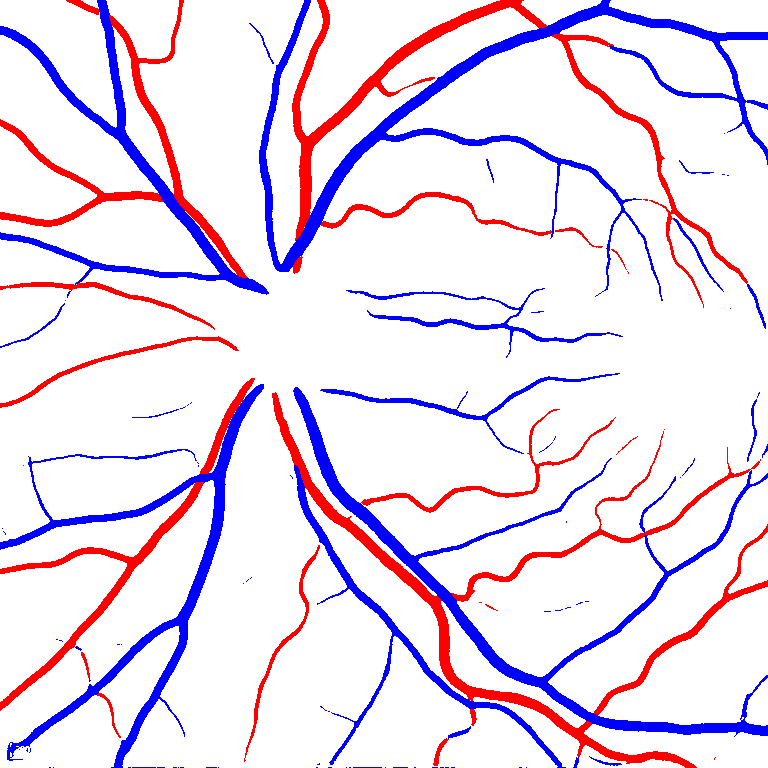

As reported in Table IV, we compared the SegRAVIR model against competing deep learning-based segmentation approaches on the RAVIR dataset. Evidently, SegRAVIR outperforms these methods as judged by all metrics for artery and vein classes with a healthy margin. In terms of Dice score, SegRAVIR outperforms CE-NET, IterNet and AG-Net by , and for artery segmentation and by , and for vein segmentation, respectively. Fig. 4 presents a qualitative comparison of the semantic segmentation outputs of SegRAVIR, CE-Net, and U-Net. Specifically, SegRAVIR yields more accurate vessel topology (i.e., thickness and orientation) segmentation with higher pixel-wise classification accuracy.

Table V presents quantitative performance benchmarks of SegRAVIR and other competing approaches for retinal artery and vein classification on the RITE dataset [11]. SegRAVIR outperforms previous state-of-the-art approaches in terms of accuracy, sensitivity, and specificity. Fig. 5 provides a qualitative comparison between segmentation outputs of SegRAVIR and the method of Hemelings et al. [40] on the RITE test set.